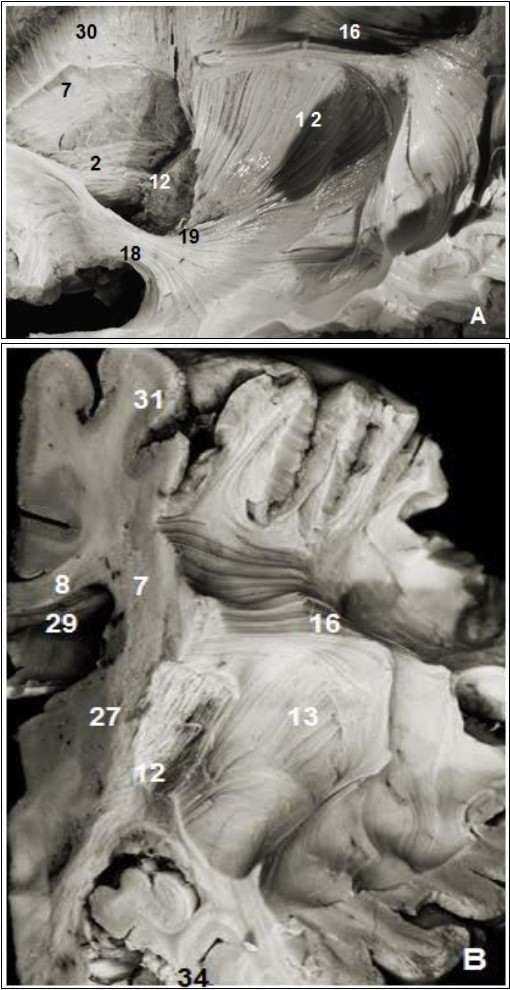

Figure 2.Subependymal stratum: (A) lateral view of right hemisphere and (B) medial view of left hemisphere. 1.Thalamus, 2. Anterior thalamic radiation, 7. Subependymal substratum, 4. Ependymal membrane, 6. Lateral ventricle, 11. Splenium of corpus callosum, 21. Cingulum, 30. Corona radiata, 32. Parietal pole, 33. Frontal pole, 35. Occipital pole, 36 tract optic

Subependymal stratum: (A) lateral view of right hemisphere and (B) medial view of left hemisphere. 1.Thalamus, 2. Anterior thalamic radiation, 7.  Subependymal substratum, 4. Ependymal membrane, 6. Lateral ventricle, 11. Splenium of corpus callosum, 21. Cingulum, 30. Corona radiata, 32. Parietal pole, 33. Frontal pole, 35. Occipital pole, 36 tract optic

Figure 4.(A) Lateral view of left cerebral hemisphere after dissection and (B) coronal view. 2. Anterior thalamic radiation, 7. Subependymal stratum, 8. Corpus callosum, 12. Internal capsule, 13. External capsule, 13. SLF, 15. Corona radiata, 16. Uncinate fasciculus, 19. Inferior frontal occipital fasciculus, 27. Putamen, 28. Globus pallidus, 29. lateral ventricle, 31. Parietal pole, 34. Temporal pole.

(A) Lateral view of left cerebral hemisphere after dissection and (B) coronal view. 2. Anterior thalamic radiation, 7. Subependymal stratum, 8. Corpus callosum, 12. Internal capsule, 13. External capsule, 13. SLF, 15. Corona radiata, 16. Uncinate fasciculus, 19. Inferior frontal occipital fasciculus, 27. Putamen, 28. Globus pallidus, 29. lateral ventricle, 31. Parietal pole, 34. Temporal pole.